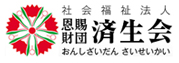

脳ドック:22,000円(がんドック御利用の方:14,300円)

頭部(MRI・MRA)+頚部(MRA)

数種類の脳MRI(磁気共鳴画像)、2方向の脳血管MRA(磁気共鳴血管画像)を、モニター上で回転して立体的に観察し、異常がないか検査します。

レポートによる結果報告となります。

もの忘れドック:27,500円(がんドック御利用の方:19,800円)

「もの忘れ」が単なるもの忘れなのか健康障害(脳血管障害・アルツハイマー病などの種々の病気)によるものなのかを早期発見するものです。

- MRI(頭部MRI・MRA・頚部MRA)検査

- VSRAD(海馬の萎縮の程度)

放射線科専門医による結果説明があります。(後日)